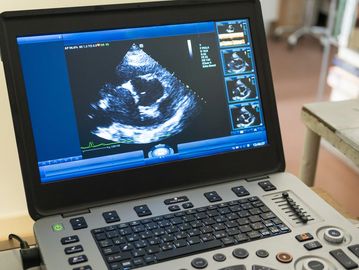

At Grove Small Animal Hospital, we’re excited to offer abdominal ultrasound services to provide a deeper look inside your pet’s health. Ultrasound is a gentle, non-invasive way to evaluate organs such as the liver, kidneys, bladder, and more—helping us detect and monitor internal conditions without the need for surgery.

Echocardiogram Services to come in 2026!